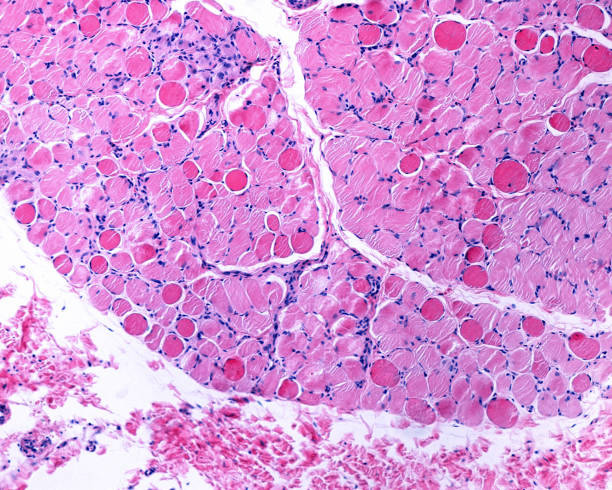

SonoThera is advancing its therapeutic programs in several areas: muscle, kidney, liver, heart, and CNS.